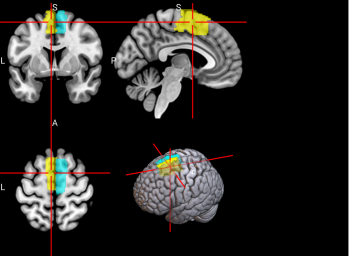

19

L Superior

frontal gyrus, medial (SFGmedial)

The medial superior frontal gyrus is involved in working memory and other higher cognitive functions [59]. The right medial superior frontal gyrus has especially been noted to function in redirecting attention [63].

/word/media/image12.png/word/media/image12.png